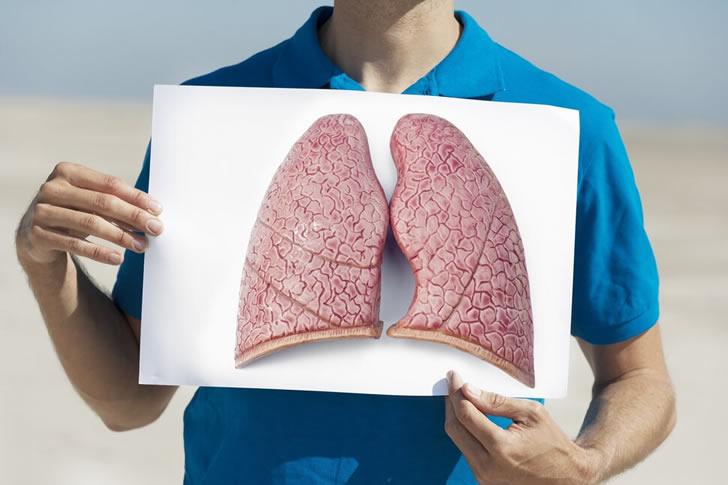

Dealing with lung cancer treatment can be overwhelming. This guide offers valuable advice to help you manage the process successfully, improve your quality of life, and foster hope.

Knowing your treatment options is crucial. Lung cancer treatments vary, ranging from surgery, chemotherapy, radiation therapy, to targeted therapy and immunotherapy. Your healthcare team will guide you through the very effective treatments tailored to your specific condition.